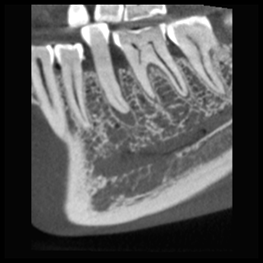

Wysoka rozdzielczość i duża dawka nie zawsze są niezbędnymi standardami i często mniej znaczy więcej. Na przykład obrazowanie ultraniskodawkowe Planmeca jest niezbędne do uwidocznienia kanału nerwu żuchwowego przy planowaniu implantów i ekstrakcji zębów mądrości. Wszystko to można osiągnąć przy wyjątkowo niskich dawkach.

Rozdzielczość HD

wielkość woksela 150 μm, dawka pacjenta ~134 μSv

Bardzo drobne szczegóły, duża dawka.

Rozdzielczość HD przy ultraniskiej dawce

wielkość woksela 150 μm, dawka pacjenta ~32 μSv

Duża szczegółowość, średnia dawka

Normalna rozdzielczość

wielkość woksela 200 μm, dawka pacjenta ~86 μSv

Normalna rozdzielczość przy ultraniskiej dawce

wielkość woksela 200 μm, dawka pacjenta ~20 μSv

Duża szczegółowość, niska dawka

Rozdzielczość dla niskiej dawki

wielkość woksela 400 μm, dawka pacjenta ~30 μSv

Mniejsza szczegółowość, niska dawka

Rozdzielczość dla niskiej dawki przy dawce ultraniskiej

wielkość woksela 400 μm, dawka pacjenta ~6 μSv

Mała szczegółowość, bardzo niska dawka